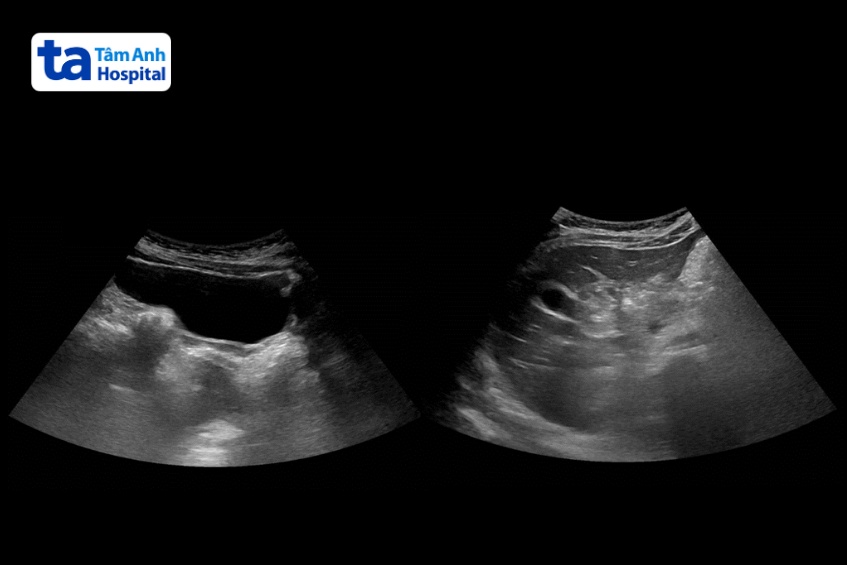

Bệnh nhi được siêu âm ổ bụng để chẩn đoán phân biệt với viêm ruột. ThS.BS.CKI Hạp Tiến Lộc, khoa Nhi, cho biết kết quả xét nghiệm nồng độ cortisol trong máu bệnh nhi giảm còn 110 nmol/L (bình thường ở khoảng 138 – 690 nmol/L). Chẩn đoán bị hội chứng cushing do cơ thể tiếp xúc với một lượng lớn thuốc chứa corticoid trong thời gian dài dẫn đến ức chế bài tiết hormone cortisol.